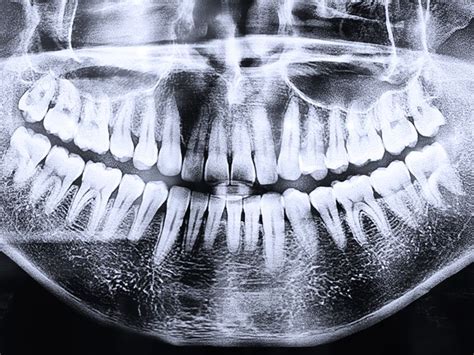

Exploración Radiográfica:

Se le realizó la exploración radiográfica de la cual os presento la ortopantomografía y la radiografía periapical.

Radiografía panorámica (ortopantomografía)

- ¿Indica los dientes que presentan tratamiento previo y las ausencias presentes en la ortopantomografía?

- ¿Qué dientes presentan patologías y qué tipo de patología?

- ¿Cuál ha sido el motivo del fracaso que se presenta en la RX periapical?

- Sin entrar en mucho detalle ¿Qué tipo de tratamientos le recomendarías a esta paciente para sustituir los dientes que le faltan?

- Si la paciente te pregunta ¿doctor de todos estos tratamientos que me ha indicado cuál es el mejor? ¿Qué respuesta le darías?